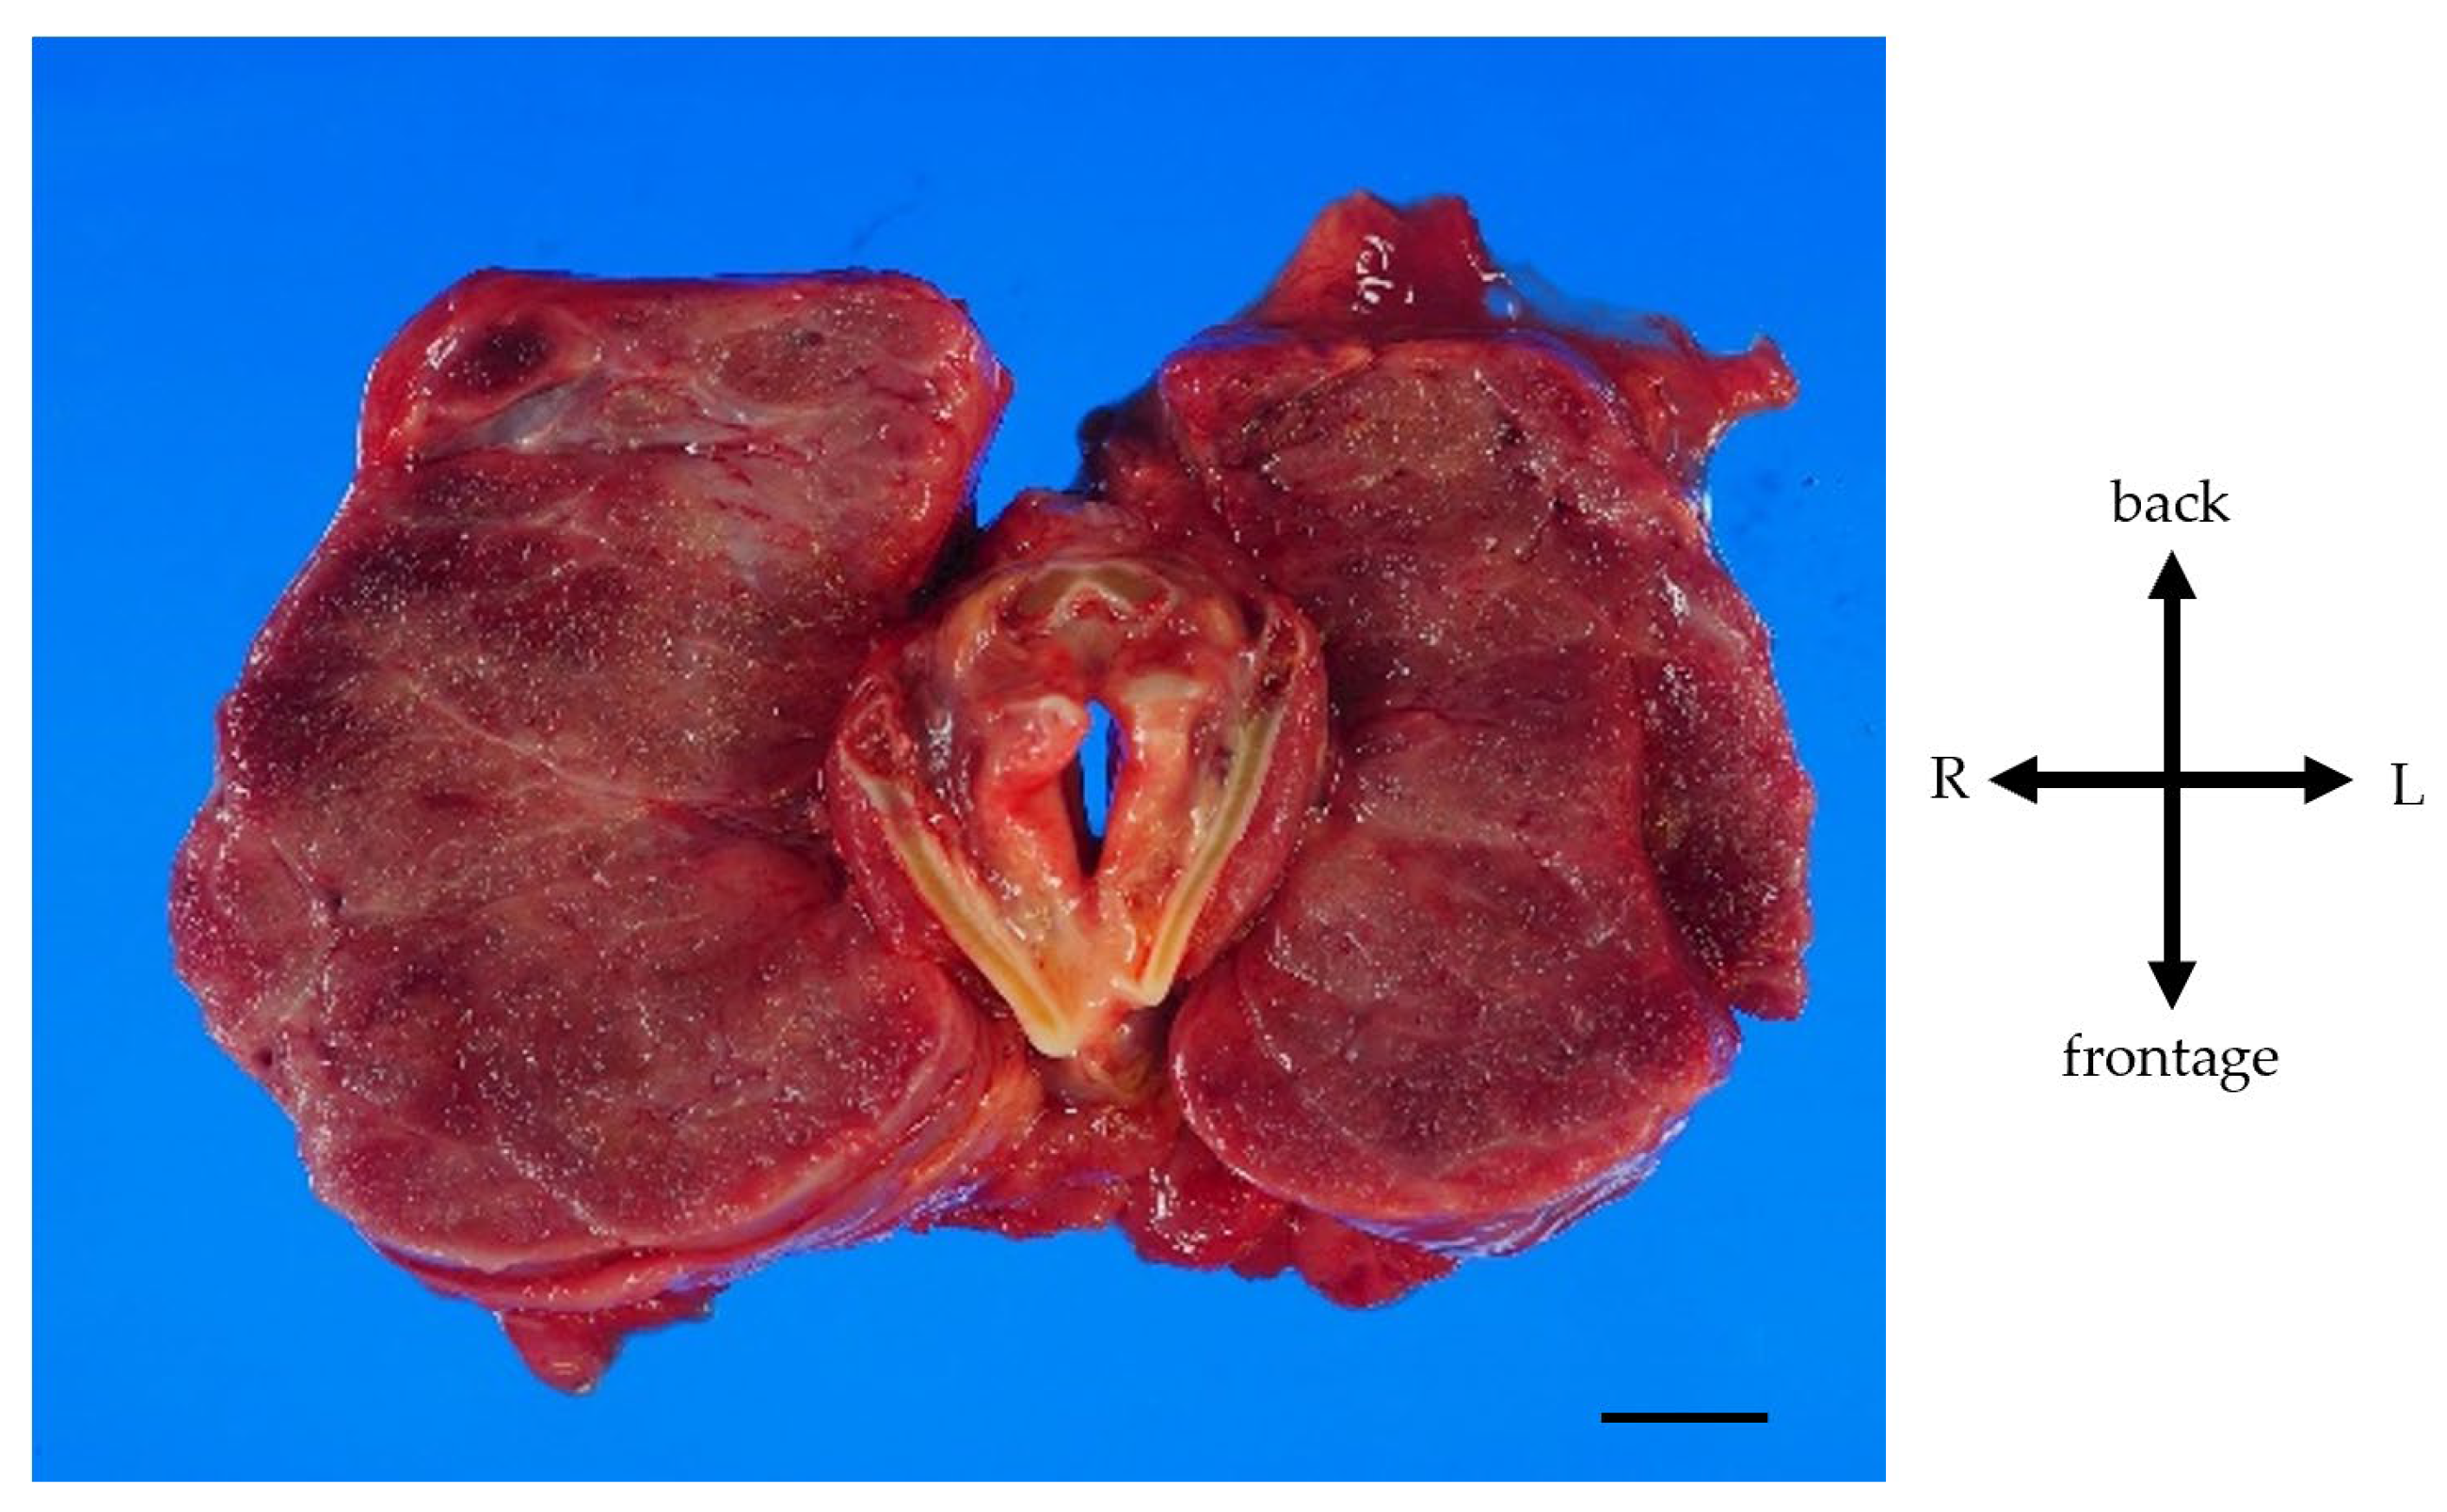

A Case of Giant Goiter Associated with Airway Stenosis Caused by Long-Term Intravenous Epoprostenol Therapy for Idiopathic Pulmonary Arterial Hypertension

2. Case Report